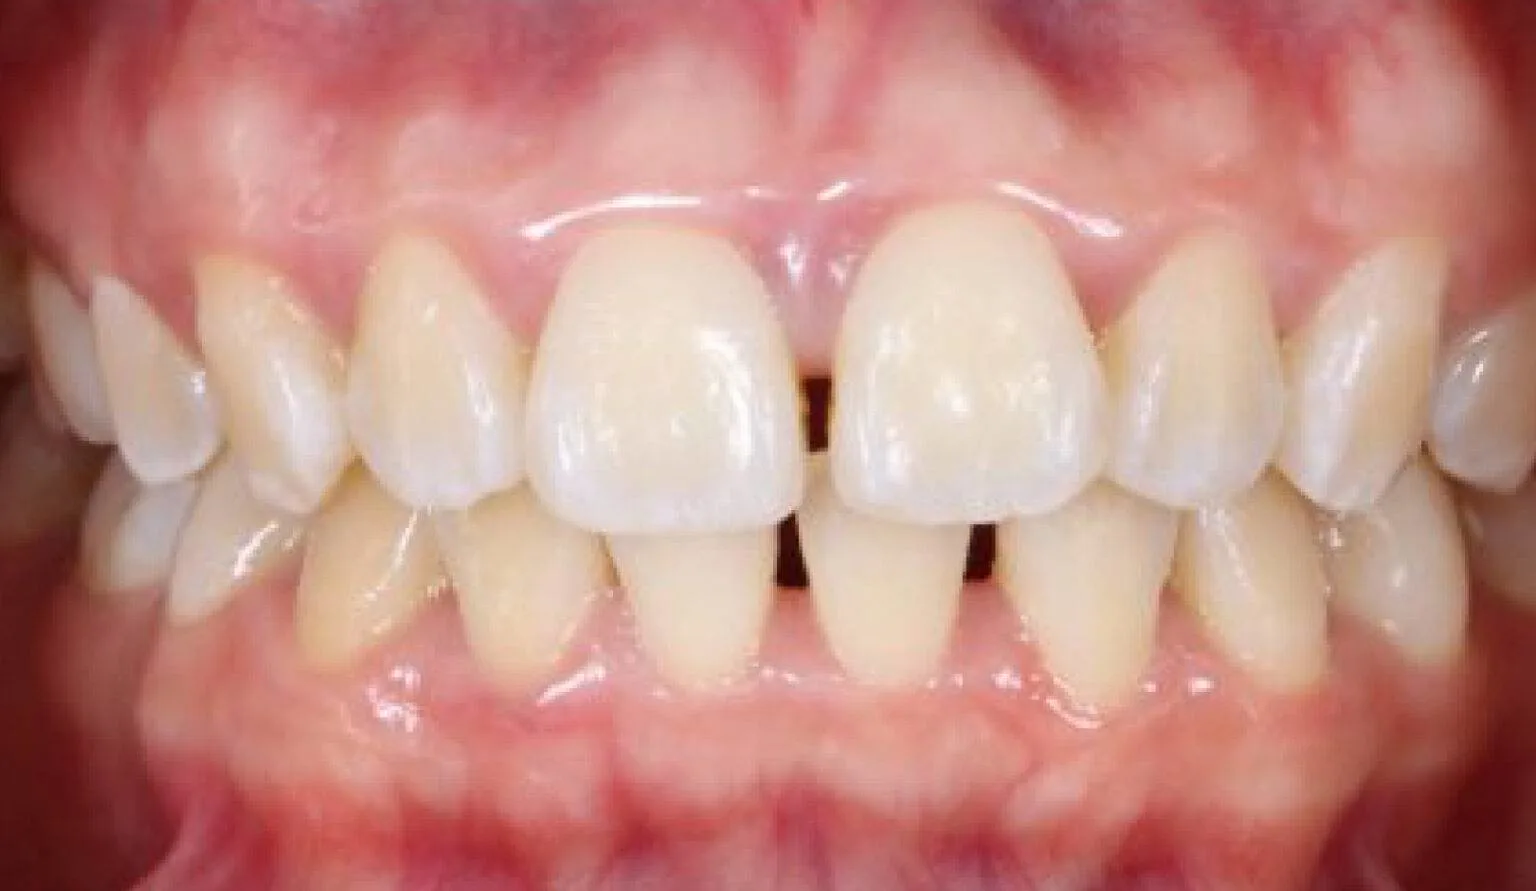

This is where there is spacing (gaps) present between the teeth. These spaces usually appear between the two upper or lower front teeth – this is known as a Diastema. A diastema usually happens due to reasons such as:

• A mismatch of the size of the jawbone and the teeth.

• A high labial frenum attachment -if you have a high labial frenum attachment then you could be suitable for a frenectomy and then orthodontics afterward to resolve this.

• Missing or undersized teeth – when some teeth are missing or smaller than others this can cause a diastema to develop. This is common when the upper lateral incisors are miss??

• Thumb sucking as a child is also a common reason for spacing in between teeth and diastema, this is due to the teeth pulling forward from the unnatural force.

A diastema isn’t seen as a ‘dental problem’ they are usually harmless and need no correction. Some people see a diastema as a characteristic that adds personality to their smile, like Madonna for example.

However, with dental spacing, we usually hear complaints of food becoming stuck in between the teeth, or in some cases, people don’t like the aesthetics of spacing or diastema. In that case, orthodontic treatment can be done to correct this.

Before & After Invisalign® Gallery